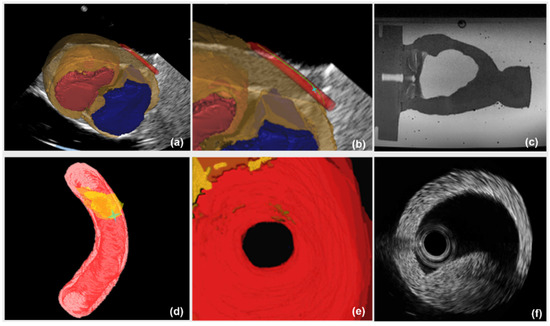

The registration results of 2D US-3D US images, 3D US-3D MR images and final 2D US-3D MR images are shown in Figure 6. The registration accuracy of 2D US-3D MR images was quantitatively evaluated by calculating the target registration error (TRE). Ten contour points of ventricle in 2D US and the corresponding contour points of ventricle in 3D MR model were manually delineated by a surgeon to calculate TRE. TRE is the average Euclidean distance of these corresponding contour points. A mean TRE of 2.70 mm (range 1.05–3.67 mm) is obtained during 2D US-3D MR image registration.

The image guidance interface and information during the intervention are illustrated in Figure 10. Under the guidance of a global navigation map (Figure 10a–c), the relative position between interventional catheter and 3D cardiac structure is displayed intuitively to navigate the catheter to the target. However, there is the limitation that the morphological information of aortic model, especially the lesion’s position, is blurred (Figure 10c). On one hand, to evaluate the vessel reconstruction error of global information, we measured the average outer radius of manually reconstructed aortic model from global MR image, and compared the average outer radius with the actual outer radius of aortic phantom (4.5000 mm). We selected 40 transverses of the reconstructed aortic model to acquire an average outer radius. The resolution of MR images is 0.4871 mm and the acquired reconstruction error of global navigation is 1.1241 mm. On the other hand, the catheter was navigated to the target using global information, and the distance between the catheter arrival position and the target was measured by using coronal and sagittal X-ray projections images from C-arm (Fluoroscan Insight, HOLOGIC, Boston, MA, USA). This distance is treated as targeting error of global navigation (See Figure 11a) and the acquired targeting error is 2.8701 mm.

Comparatively, in the case of a global map plus local navigation information, the user can be guided to insert catheter along the preoperative planning path. Meanwhile, the local navigation information (Figure 10d–f), further provides the user with critical details of the target point. Firstly, to evaluate the vessel reconstruction error of local navigation information, we calculated the average outer radius of the automatically reconstructed aortic model from segmented IVUS images, and compared this average outer radius with the actual radius of aortic phantom. The resolution of IVUS images is 0.0175 mm and the acquired reconstruction error of local information is 0.2217 mm. Secondly, to evaluate the targeting error of catheter intervention, we captured coronal and sagittal X-ray projections when the catheter was navigated to the target by using global plus local information. These projections images are measured (See Figure 11b) and the acquired targeting error is 1.7214 mm. This experiment shows that the new US navigation system which integrates global and local information can improve upon the navigation system that relies on a global navigation map alone.

Recently, 2D US images have been widely used in minimally invasive cardiac procedures due to its real-time imaging capabilities. However, it is difficult to relate the 2D US images to anatomical context due to the limit of image quality. 3D US image may overcome this problem to some degree, but it performs 3D imaging at the cost of decreased temporal resolution and only provides a narrow field of view. Therefore, we propose to use high-quality 3D context from MR images to enhance 2D US images through image registration, providing a global navigation map for surgeons. To solve the difficulty of 2D US-3D MR image registration, we develop a novel registration method based on calibrations of 2D and 3D US probes. On the one hand, we acquire the small probes’ calibration reproducibility errors (calibration error of 2D US probe: 0.61 mm, calibration error of 3D US probe: 1.42 mm). On the other hand, in Figure 6b, the contours of ventricles in 2D US and 3D MR images achieve a good agreement after registration, which qualitatively demonstrates that the proposed 2D US-3D MR image registration method is effective. A TRE of 2.70 mm is obtained for US and MR image registration. Through registration, interpretability of 2D US images is improved within the 3D anatomical context provided by MR images. Therefore, a global navigation map by integrating 2D US and 3D MR images is achieved (Figure 10a).

Figure 6. Registration results of 2D US-3D US, 3D US-3D MR and final 2D US-3D MR images (red volume is the left ventricle model; blue volume is the right ventricle model). (a) Registration results of 3D US-3D MR images; (b) Registration results of 2D US-3D MR images; (c) Registration results of 2D US-3D US images.

Figure 10. Image guidance interface and information. (a) a global navigation map from 2D US-3D MR registration; (b) enlarged view of a global map at the region of aorta, green curve is the preoperative planning path, asterisk denotes the position of interventional catheter; (c) collected MR image; (d) local navigation information with morphological characteristics of aorta. Dark yellow volume is lesion; (e) virtual visual image from endovascular view; (f) collected IVUS image.